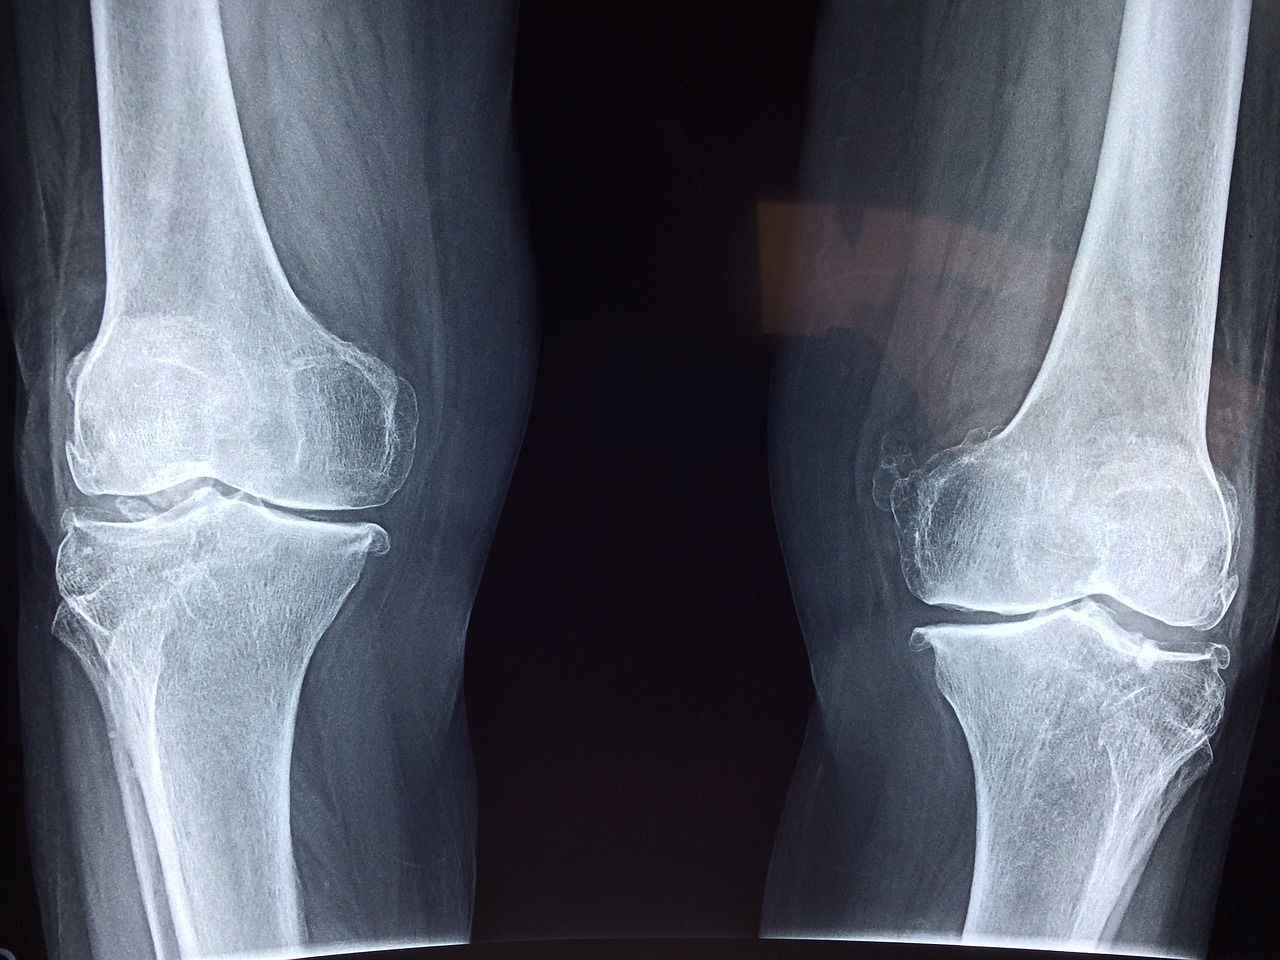

원판형 반월상연골기형은 반월상연골이 정상적인 C자 형태가 아닌 원반 모양으로 형성되는 선천적인 질환입니다. 이로 인해 무릎 관절의 불안정성이 증가하고, 점진적인 연골 손상이 발생할 수 있습니다. 심한 경우 관절 내 구조적인 손상과 통증이 동반되며, 치료를 위해 수술이 필요합니다. 하지만 수술만으로 완전히 회복되는 것이 아니라, 이후 체계적인 재활이 필수적입니다. 재활 과정이 제대로 이루어지지 않으면 무릎 기능이 저하되고, 재손상의 위험이 높아질 수 있습니다. 본 글에서는 원판형 반월상연골기형 수술 후 효과적인 재활 방법을 단계별로 상세히 소개해 드리겠습니다